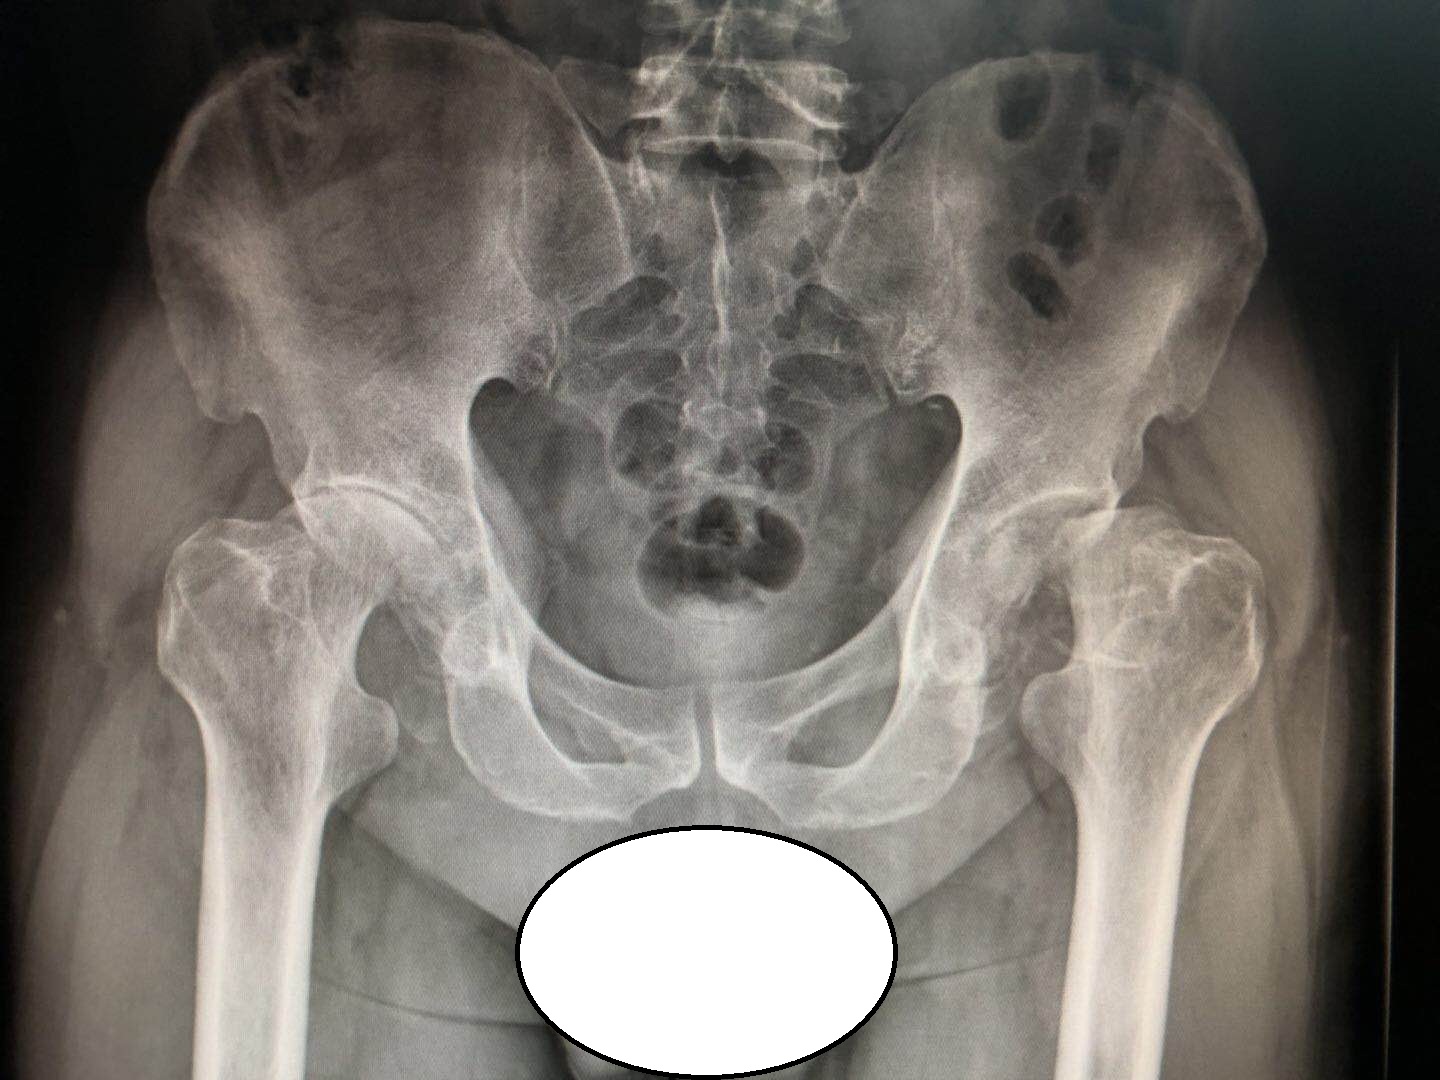

老陈的髋关节病变已经处于“晚期”!

之所以称为晚期,是因为老陈的骨盆正位片上已经看不到完整的股骨头了!

换句话说,老陈的股骨头已经塌陷了,不圆了,没法在髋臼窝里面良好的转动了......

坏死的股骨头病灶在人体持续走路、负重的情况下,会被自己的体重逐渐压塌,就会导致股骨头变扁,无法在髋臼窝里良好的转动,就像上图所示一样!